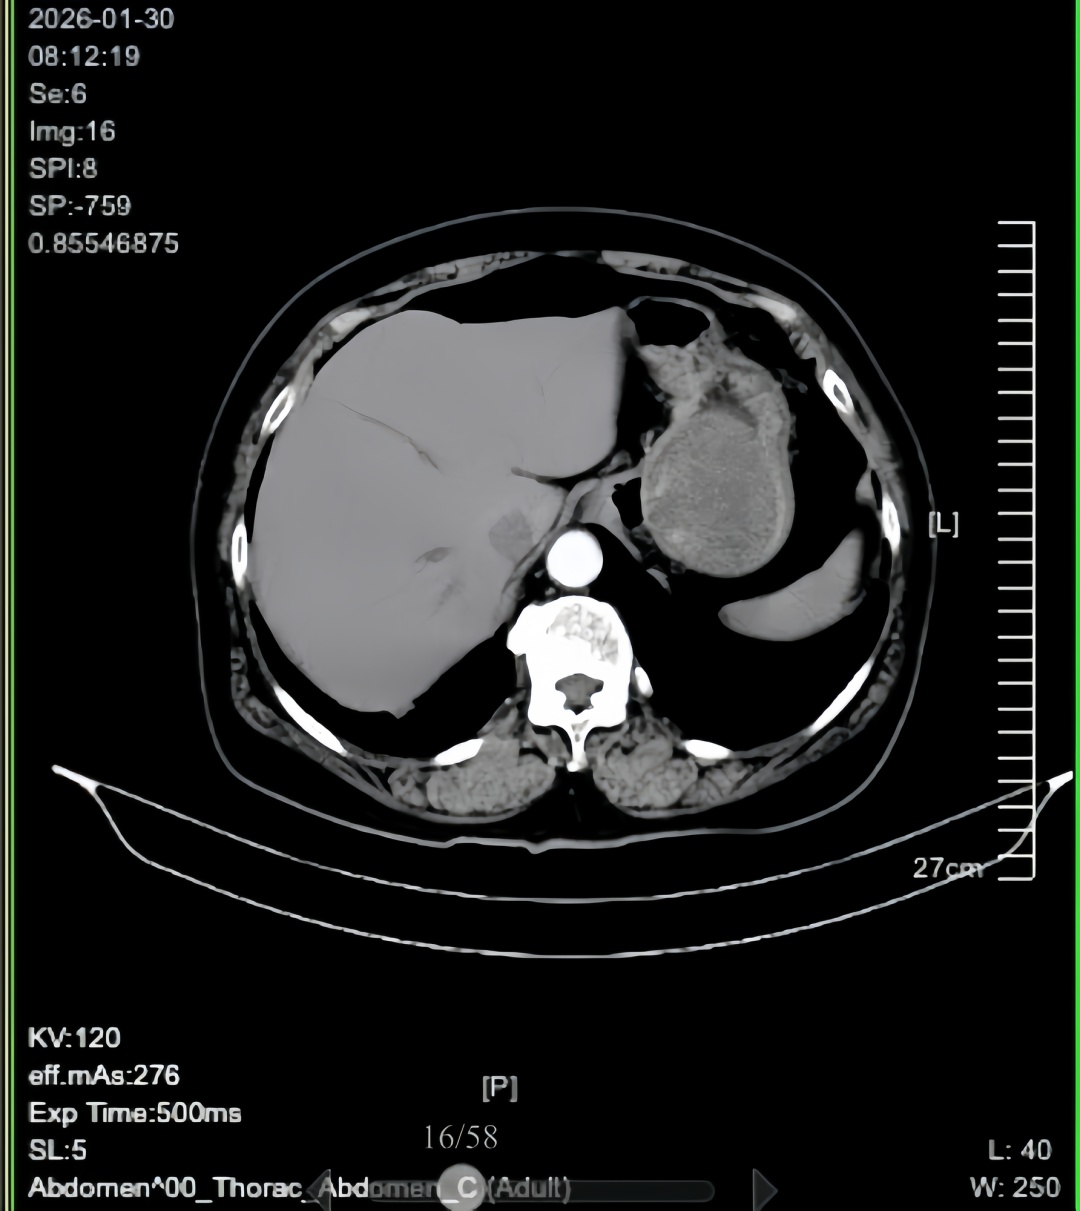

检查结果令人揪心:患者胃底部近贲门处有直径约 7cm 的巨大肿瘤,中央伴溃疡及出血,初步诊断为胃巨大间质瘤。更危急的是,患者入院时血色素仅 46g/L,远低于正常成人水平,属重度贫血,随时可能因失血性休克危及生命,救治工作刻不容缓。

面对难题,陈俏峰凭借扎实的专业功底、丰富的腹腔镜手术经验,以及对胃间质瘤诊治的深刻理解,反复研读影像学资料、推演手术流程,最终确定 “腹腔镜胃间质瘤切除术 + 胃镜支撑下贲门成型术”方案,力求在彻底切除肿瘤的同时,最大限度保护贲门功能。